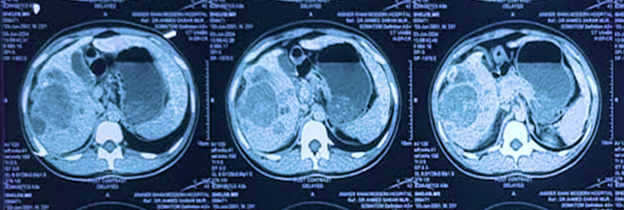

1. Triphasic CT Scan shows a giant mass in all segments of the right lobe of the liver.

1. a) TACE: Accumulation of lipiodol mixed with Doxorubicin and 2 ml water-soluble dye within the tumor. b) No dye accumulates within the tumor following embolization with PVA particles.

1. Post-TACE CT one month after TACE shows residuals within the tumor.

1. Microwave ablation was performed in the entire tumor from the medial to the lateral margin in three sessions.

1. CT scan 2 months post-MWA shows the entire tumor, including the margin, was hypotenuse, indicating complete necrosis.